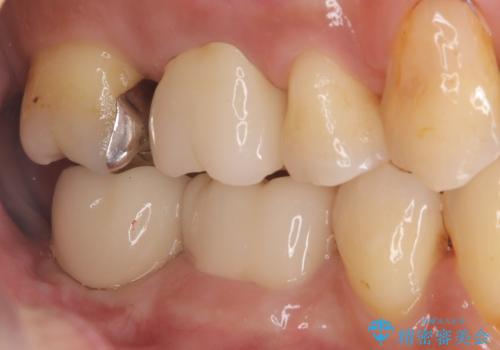

メタルクラウンを除去したところ近心面に大きな窪みとう蝕を認め、ファイバ-コアからのやり替えとしました。クラウンは審美性の良いセラミッククラウンを選択されました。

・仮歯:20,000円(税抜き)

・オールセラミッククラウン(スタンダード):110,000円(税抜き)

・ファイバ-コア:20,000円(税抜き)